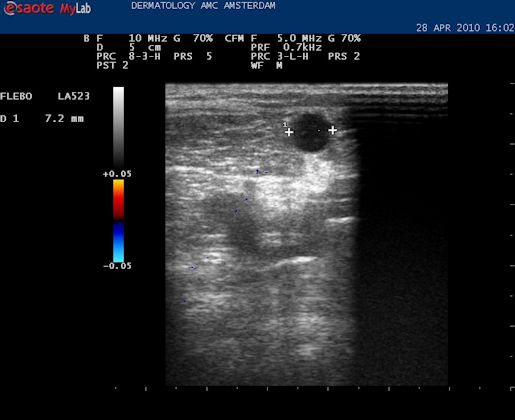

| Het is mogelijk om de diameter op te meten van het vat. Het kan handig zijn om dat te weten in verband met de therapie; of er bijvoorbeeld een VNUS catheter doorheen kan. |

| Met de duplex kan ook de reflux over het vat worden gemeten. |